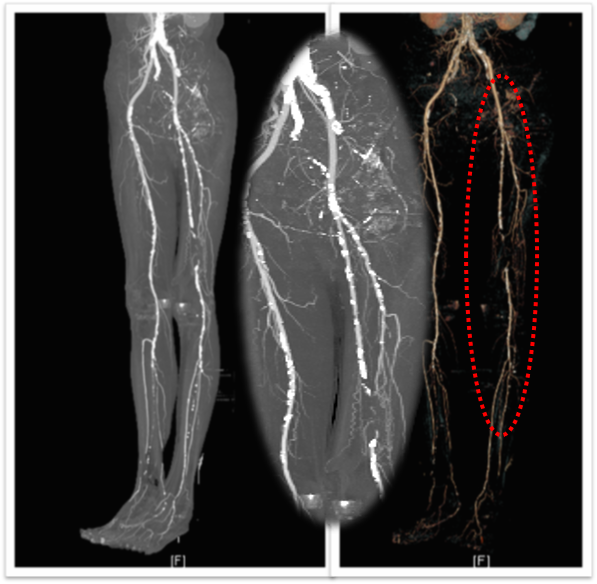

图为:股腘动脉DAART+区域性DES 最终造影

图为:2023年11月 2年后复查

2年后(2023-11)复查

下肢动脉CTA提示左股腘动脉通畅,DES区域未见内膜增生管腔丢失表现